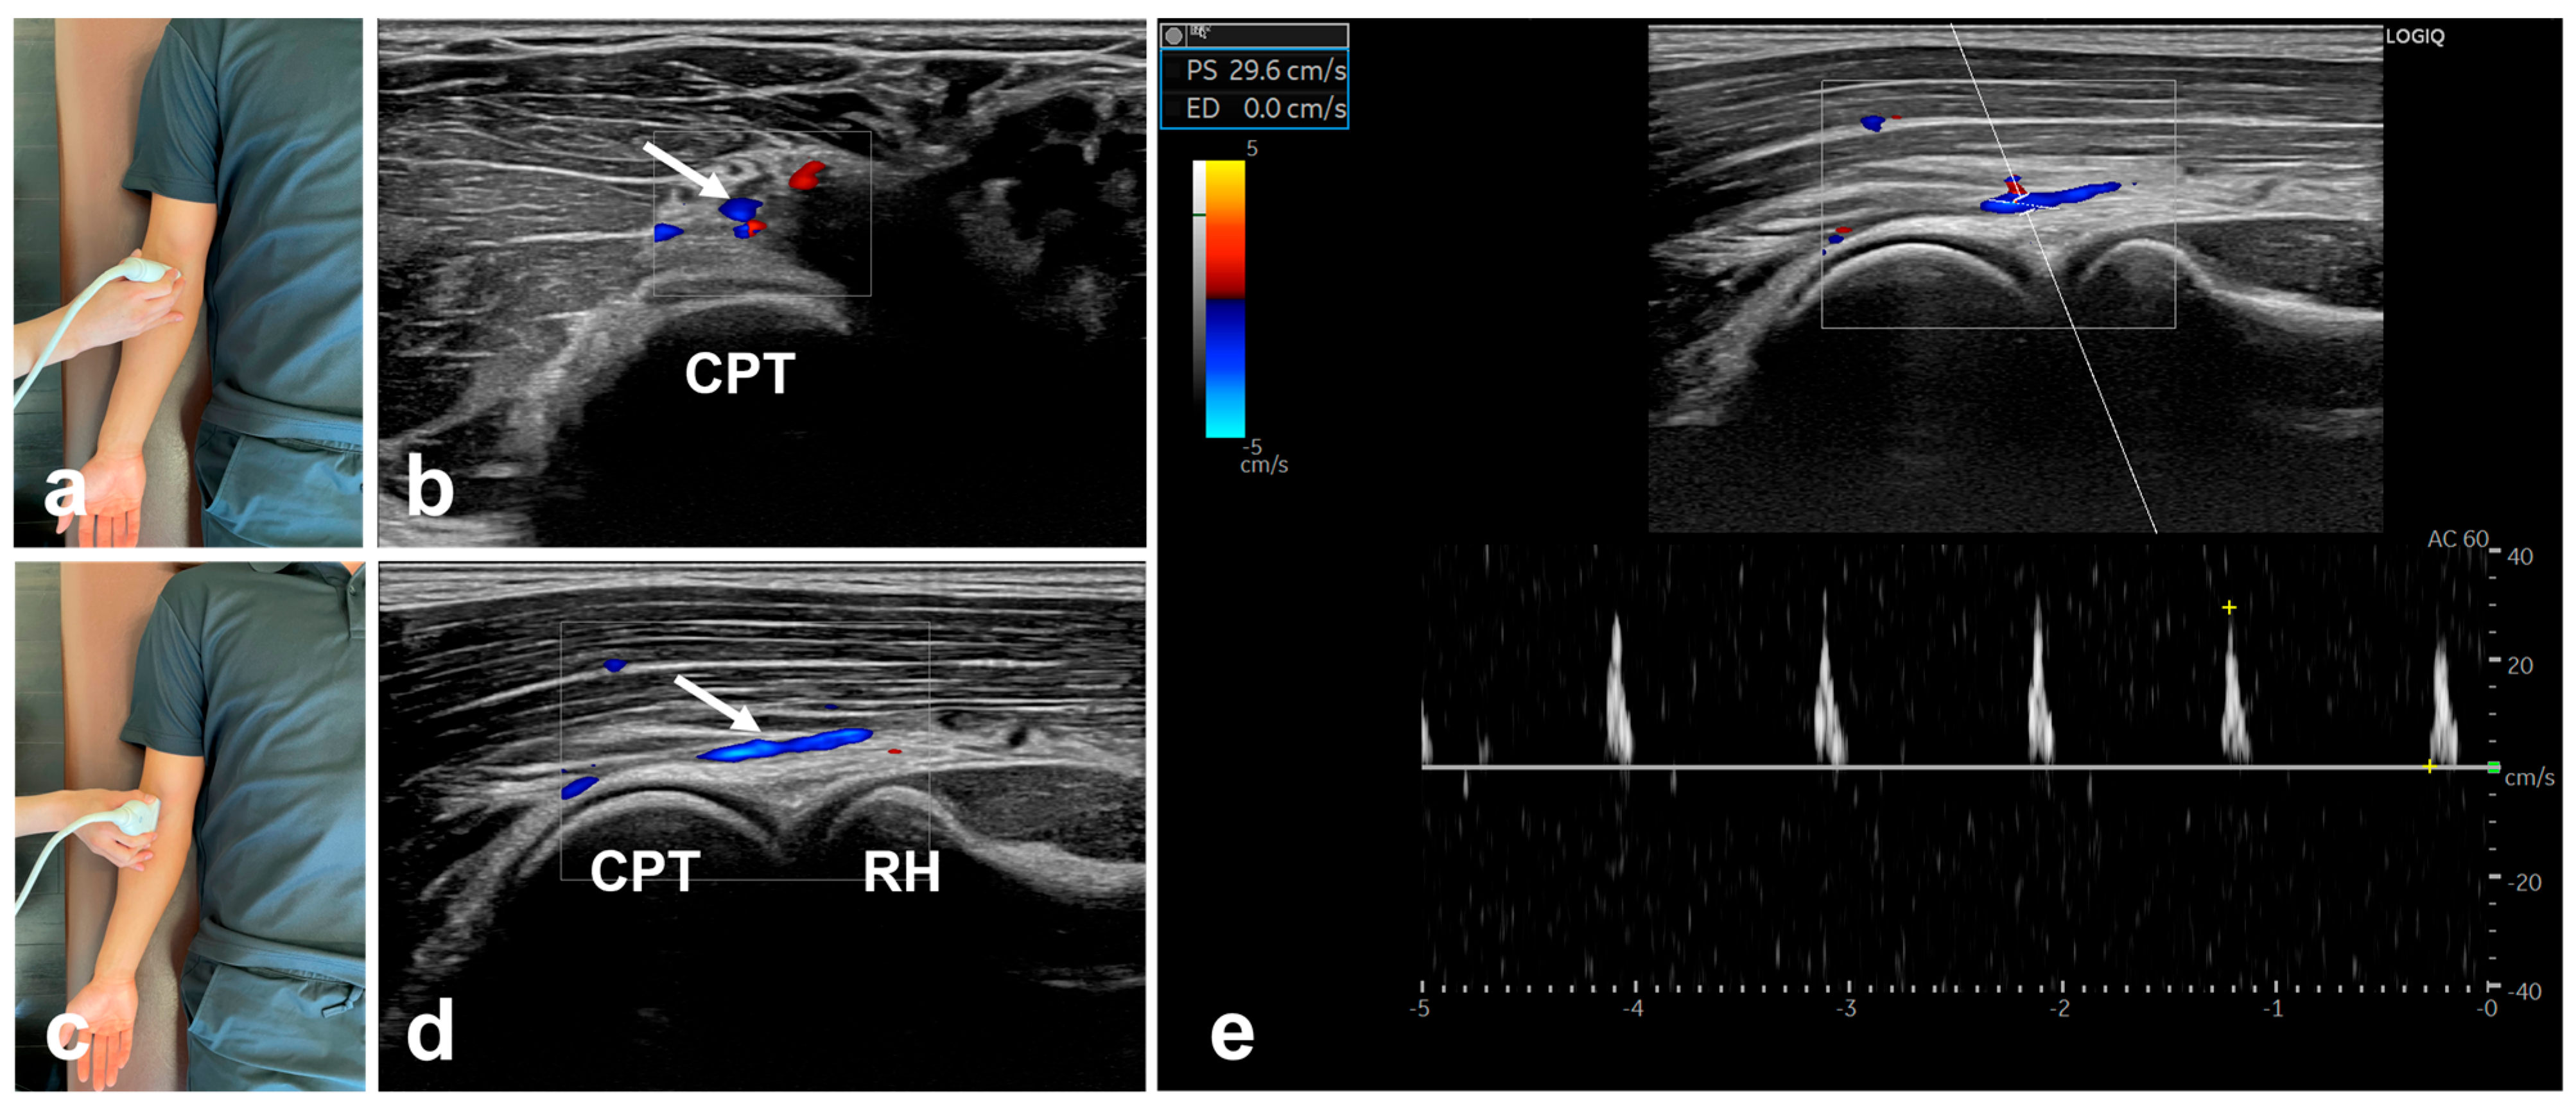

2.3. Ultrasonographic Assessments